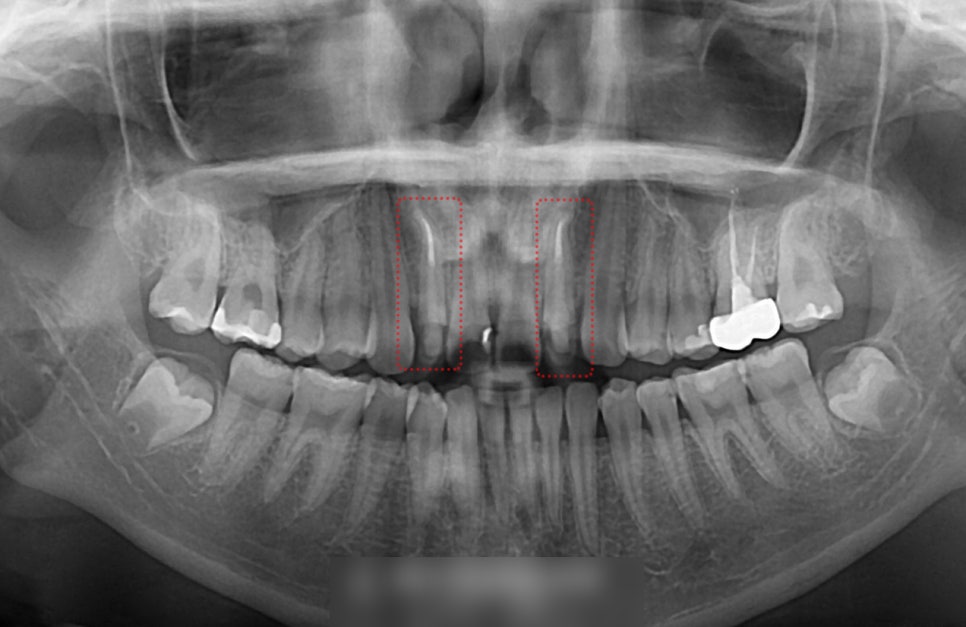

계획 수립 전 촬영한 엑스레이에서

12번과 22번에 이전에 받으신

신경치료 흔적이 눈에 띄었는데요.

이동에 필요한 공간을 만들기 위해서는

이를 뽑는 과정이 필요한데

이때 상태가 좋지 않은 곳을 우선으로 선정을 합니다.

결국 앞니 발치 교정으로 설명을 드리고

12번과 22번은 뽑은 뒤

그 공간은 자연스럽게 폐쇄를 시키며

치열을 개선해야 될 것으로 진단되었습니다.

하악 전치 또한 4개가 아닌 3개로

이전에 여러 요인들로 인해 이를 뽑았거나

치배가 형성되지 않은 것으로 판단되는데요.